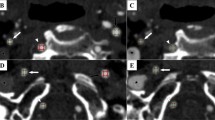

To achieve these perturbations, the original ROIs delineated by the primary reader (EPVL) were subjected to the dilation and erosion image morphological operations implemented in Python, see Fig. 6.

ROI segmentation and perturbations. Carotid CTA images were manually segmented to delineate the carotid artery. The original ROI was subjected to morphological operations: erosions and dilations aimed to assess the robustness of radiomic features to perturbations in image segmentation.

For single-slice analysis, we used a circular structuring element of radius 1, with iterations of 1–2 for ROI dilation and erosion. For multi-slice analysis, we used a spherical structuring element of radius 1, with iterations of 1–2 for ROI dilation, but only 1 iteration for ROI erosion in order to ensure that a sufficient number of pixels would be available for the downstream radiomic feature calculation after erosion. Where resegmentation was applied as a pre-processing scheme, ROI erosion was not performed, only ROI dilation to ensure that all ROIs had sufficient pixels for radiomic feature extraction, details of resegmentation are provided below.